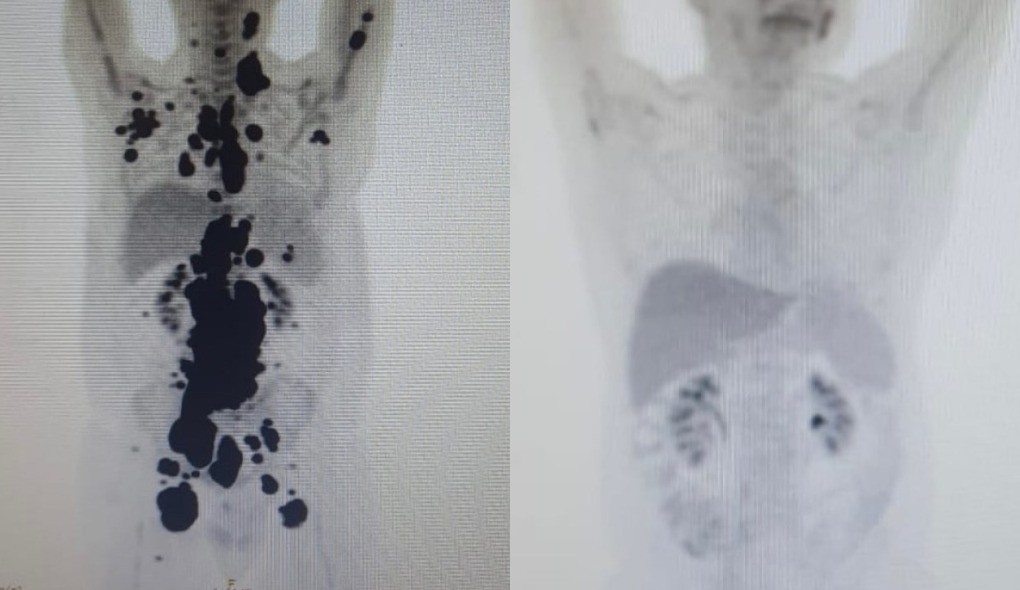

O publicitário Paulo Peregrino, que conviveu com a doença por 13 anos, obteve remissão completa em apenas um mês após receber a terapia CAR-T Cell. O caso é acompanhado pelo médico Vanderson Rocha, que destaca a rapidez e a eficácia da resposta ao tratamento. Imagens de PET Scan demonstram a redução significativa dos tumores, evidenciando o potencial da terapia.